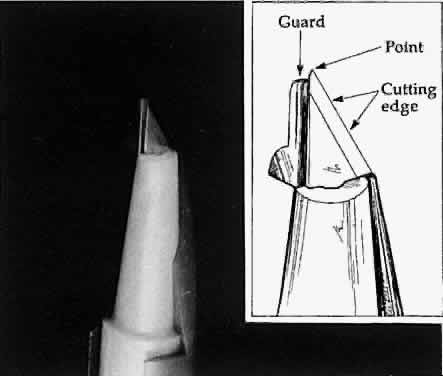

and opening the scissors' blades, or by using a spatula. Sharp dissection is needed to cut across the lamellae. It may be accomplished

with either a single blade or a scissors. When using a blade, the

surgeon must distinguish between cutting with the point of the blade

or with the cutting edge of the blade (Fig. 21). The point of the blade is a versatile cutting instrument that can produce

incisions of any shape. Because the blade point must be extremely

sharp, blades are either disposable or constructed of highly resistant

material (e.g., diamond). The surgeon can vary the amount of the cutting

edge that penetrates the tissue to make a straight versus a curved

incision.  Fig. 21. A guarded blade. The cutting edge is distinguished from the point of the

blade. The point of the blade is more versatile than the cutting edge

for producing incisions of various shapes. Fig. 21. A guarded blade. The cutting edge is distinguished from the point of the

blade. The point of the blade is more versatile than the cutting edge

for producing incisions of various shapes.